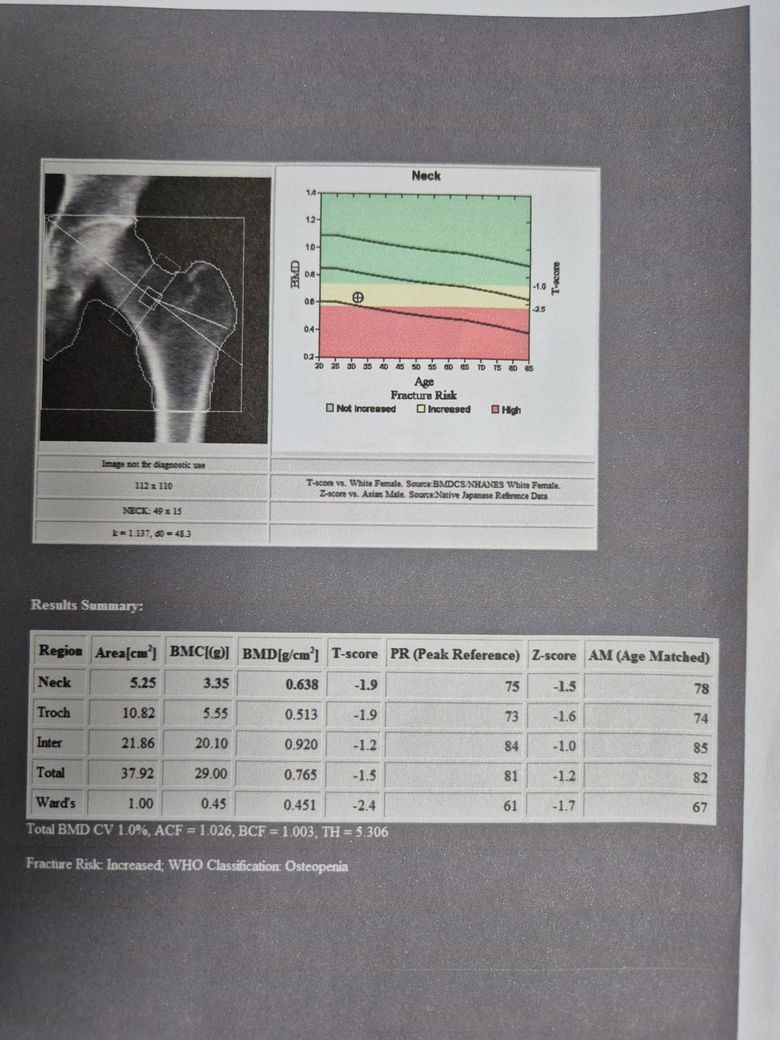

얼마전 건강검진에서 우연히 골밀도검사(대퇴부, 요추)를 받았는데 사진과 같이 골감소증이 나왔습니다.

골밀도검사지 사진첨부 했습니다.

골밀도 검사지로 보아서는 골감소증을 보이는 것으로 보입니다.